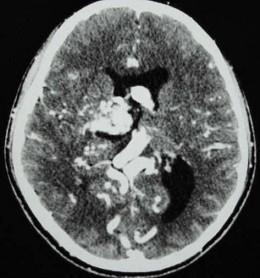

问题 男,32岁,头痛、癫痫,查体发现视乳头水肿,CT检查如图,最可能的诊断为()

选项 A.结节状硬化 B.钙化灶 C.动静脉畸形 D.少突胶质瘤 E.脑囊虫

答案 C